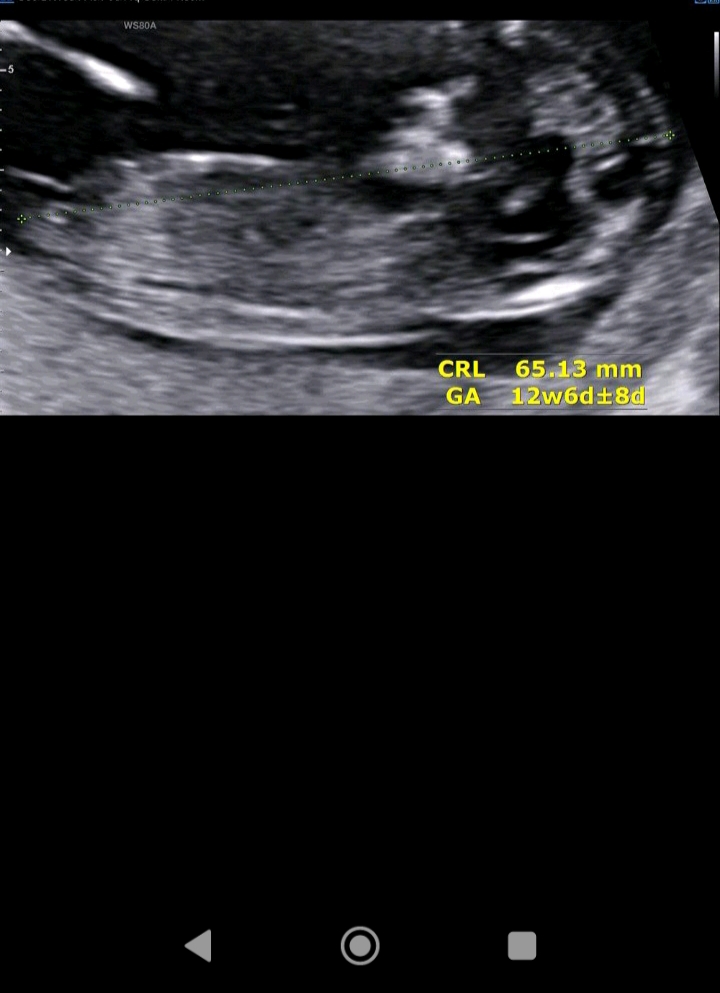

من بلد نیستم ولی حسم میگه دختر